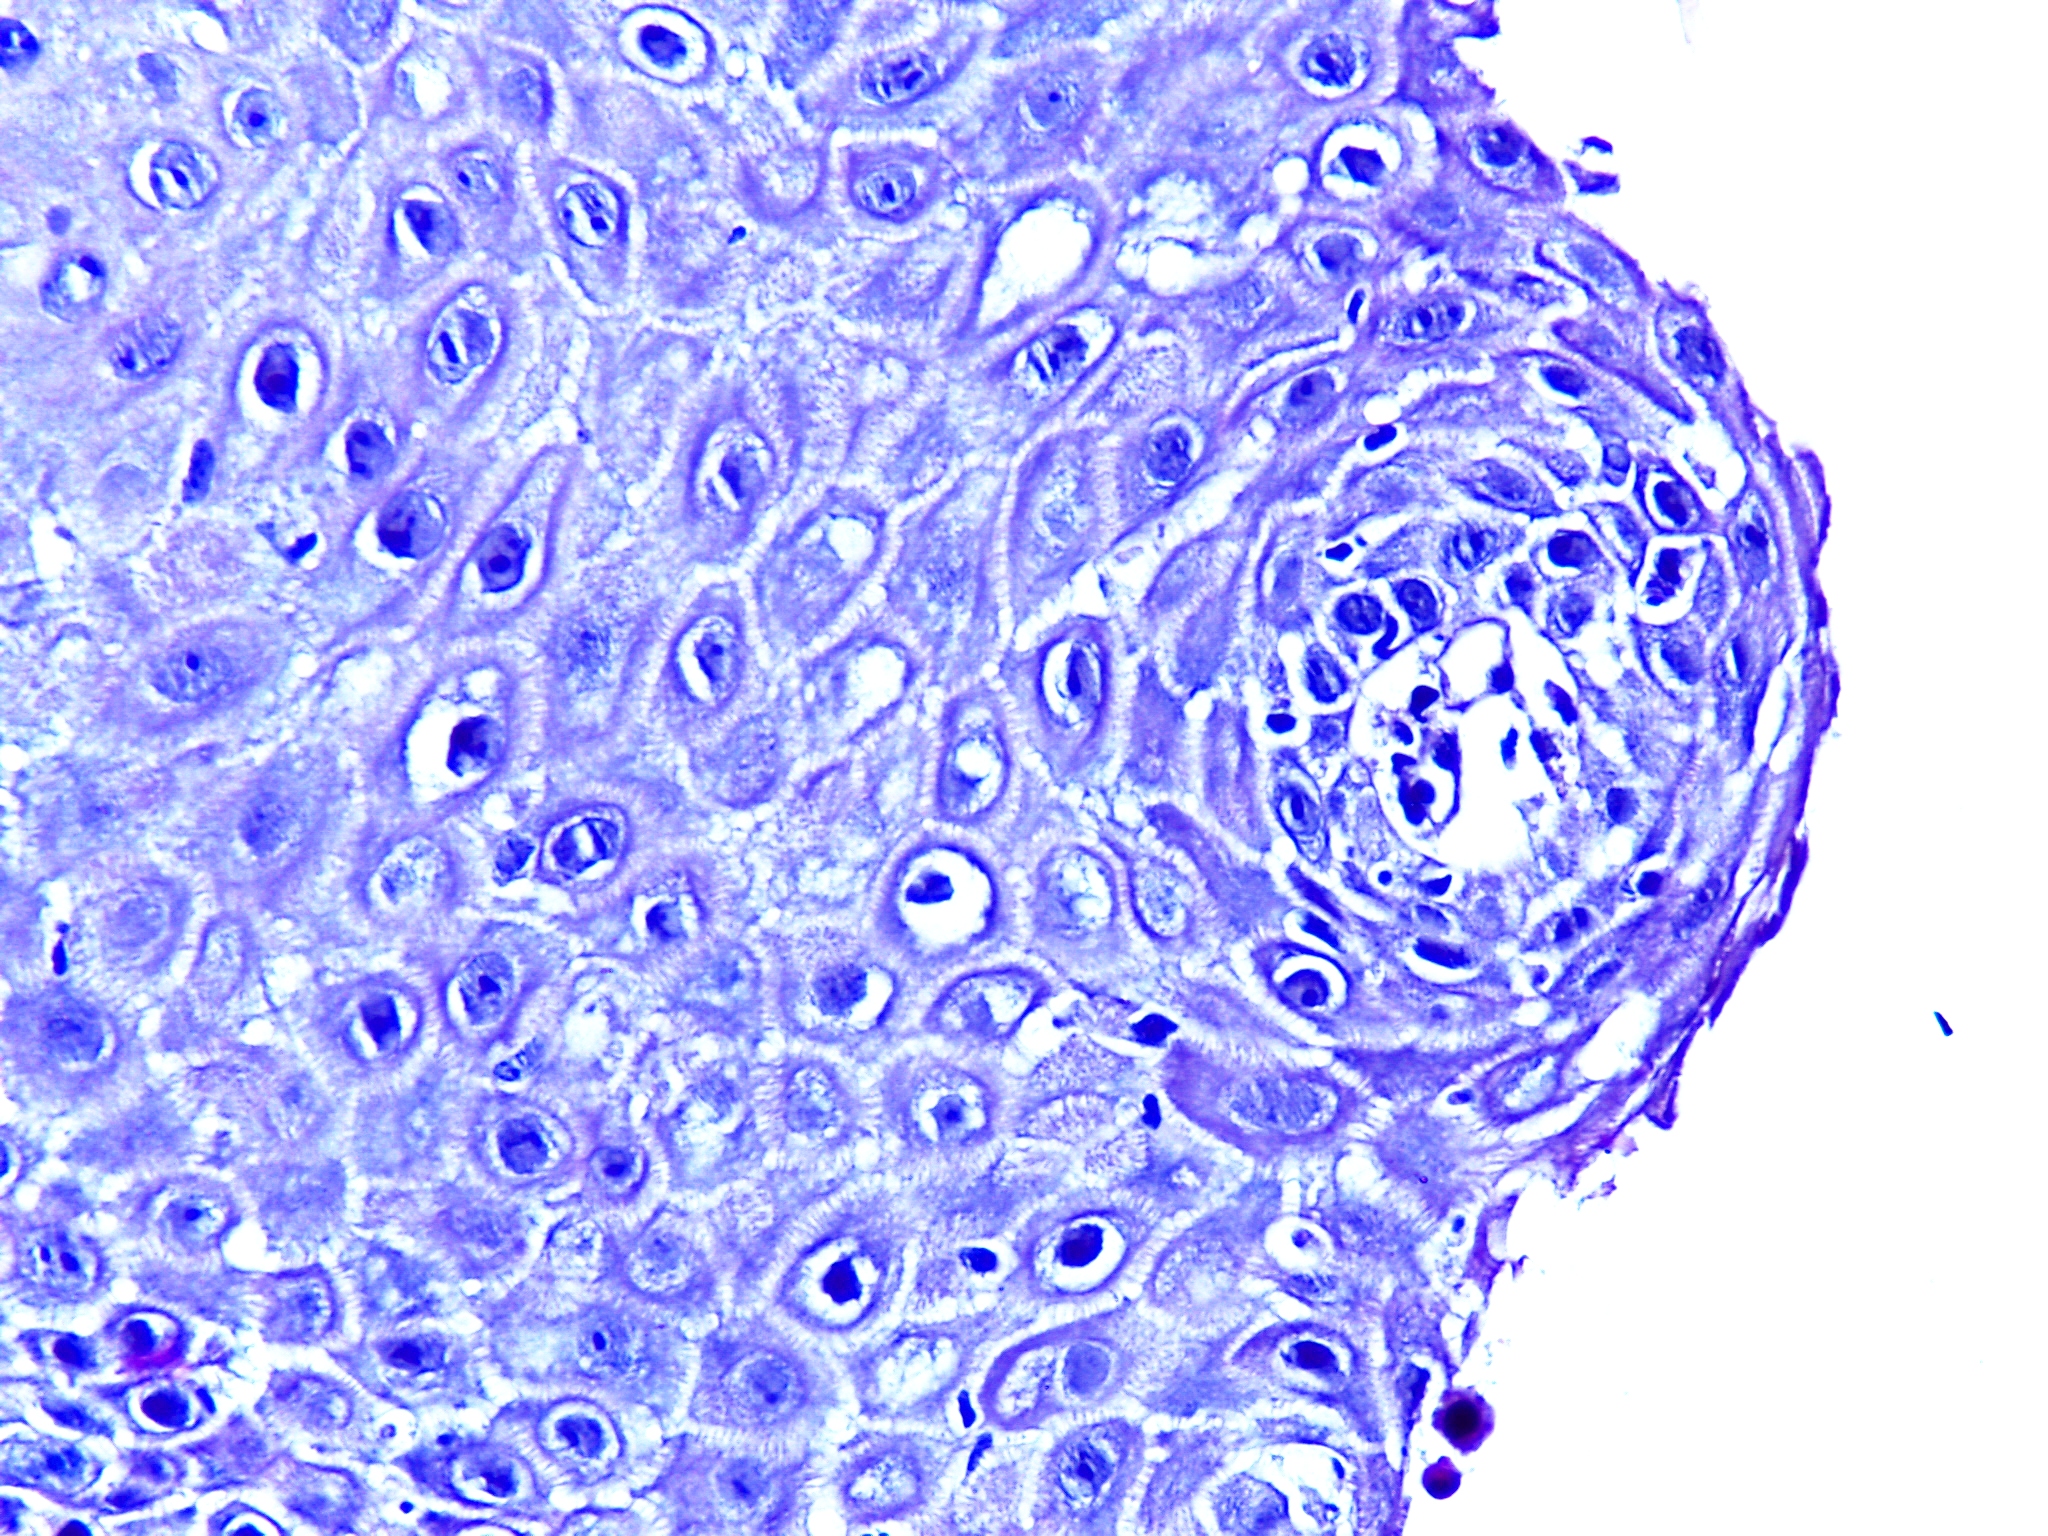

Developing Deep Learning Models for Quantitative Estimation of Reticulin Fibers in Bone Marrow Trephine Biopsy Specimens

2025-09-23

996MB

HISTOS_1000000028

250

15

14

Quick View

Data